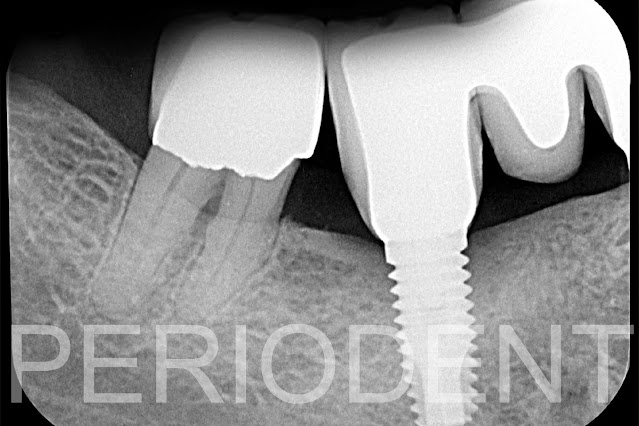

3. 2018年發現大臼齒有植體周圍炎

10. 移除原有假牙

11. 進行植牙周圍炎手術,利用ER-YAG雷射清除植體上結石及植體表面清除後,利用Open

Membrane方式作補骨